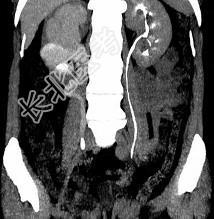

- 多项选择题患者女,44岁, 突发性胁腹部绞痛并向会阴部放射伴血尿一次。如图所示,下列说法正确的是 ( )

A、右侧肾盂肾盏扩张

B、右输尿管中上段扩张

C、右输尿管内可见沿输尿管走行的高密度影

D、右输尿管结石

E、左肾输尿管未见异常